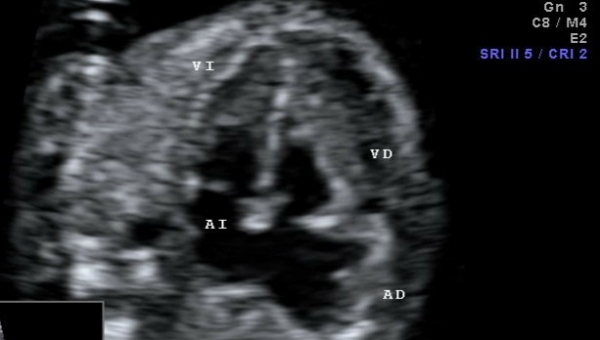

Aunque no se conoce el nivel de incidencia, el embarazo ectópico en cicatriz de cesárea previa puede ocurrir y se presenta como todo un reto para el personal médico especialista que trata el caso.

Es considerada una forma novedosa y potencialmente mortal de implantación anormal de un saco gestacional dentro del miometrio y el tejido fibroso de la cicatriz.

Hay quienes también le llaman “istmocele”, “embarazo ectópico en la cicatriz de la cesárea”. Sin embargo, algunos grupos prefieren hacer la diferencia con el embarazo ectópico “verdadero”: tubario, cornual, intersticial y cervical.